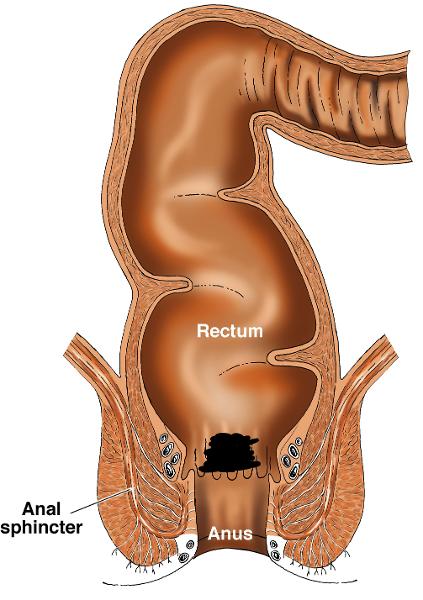

Anal Canal

Anus

Rectum